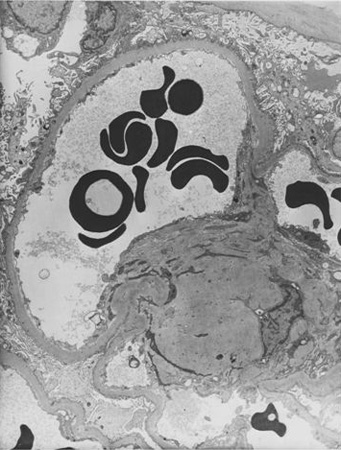

Diabetes mellitus is characterised by high glucose levels and increased glomerular pressure, both of which can cause glomerular mesangium expansion via increased mesangial stretch. Platelet-derived growth factor (PDGF) and transforming growth factor-beta (TGF-beta) mediate mesangial expansion and fibrosis via the stimulation of matrix protein (collagen and fibronectin) synthesis and decreased matrix degradation. Glucose forms advanced glycation end products (AGEs) by binding irreversibly to proteins. Over years, AGEs form crosslinks, stimulate the release of growth factors such as TGF-beta, and cause fibrosis. Angiotensin II (ATII), elevated in DKD, constricts the efferent arteriole in the glomerulus, causing high glomerular capillary pressures, and also stimulates fibrosis and glomerular inflammation. Mesangial expansion is characteristic of early diabetic glomerulosclerosis and is followed by fibrosis in the late stages. Kimmelstiel-Wilson nodules, areas of mesangial expansion on biopsy, are the hallmark of diabetic glomerulosclerosis and are seen in half of the cases of DKD. Increased glomerular basement membrane width, diffuse mesangial sclerosis, hyalinosis, microaneurysm, and hyaline arteriosclerosis are present in addition to tubular and interstitial changes.[17] Hypertension, via mesangial stretch, can aggravate progression of DKD.[Figure caption and citation for the preceding image starts]: Diabetic kidney disease: mesangial expansion due to increased mesangial matrix and decreased degradation of glycosylated collagenFrom the collection of Dr Raoul Fresco; used with permission [Citation ends].

[Figure caption and citation for the preceding image starts]: Diabetic kidney disease: at 5 o'clock - early Kimmelstiel-Wilson nodule, a rounded increase in mesangial matrix that probably originated in relation to a microaneurysmFrom the collection of Dr Raoul Fresco; used with permission [Citation ends].